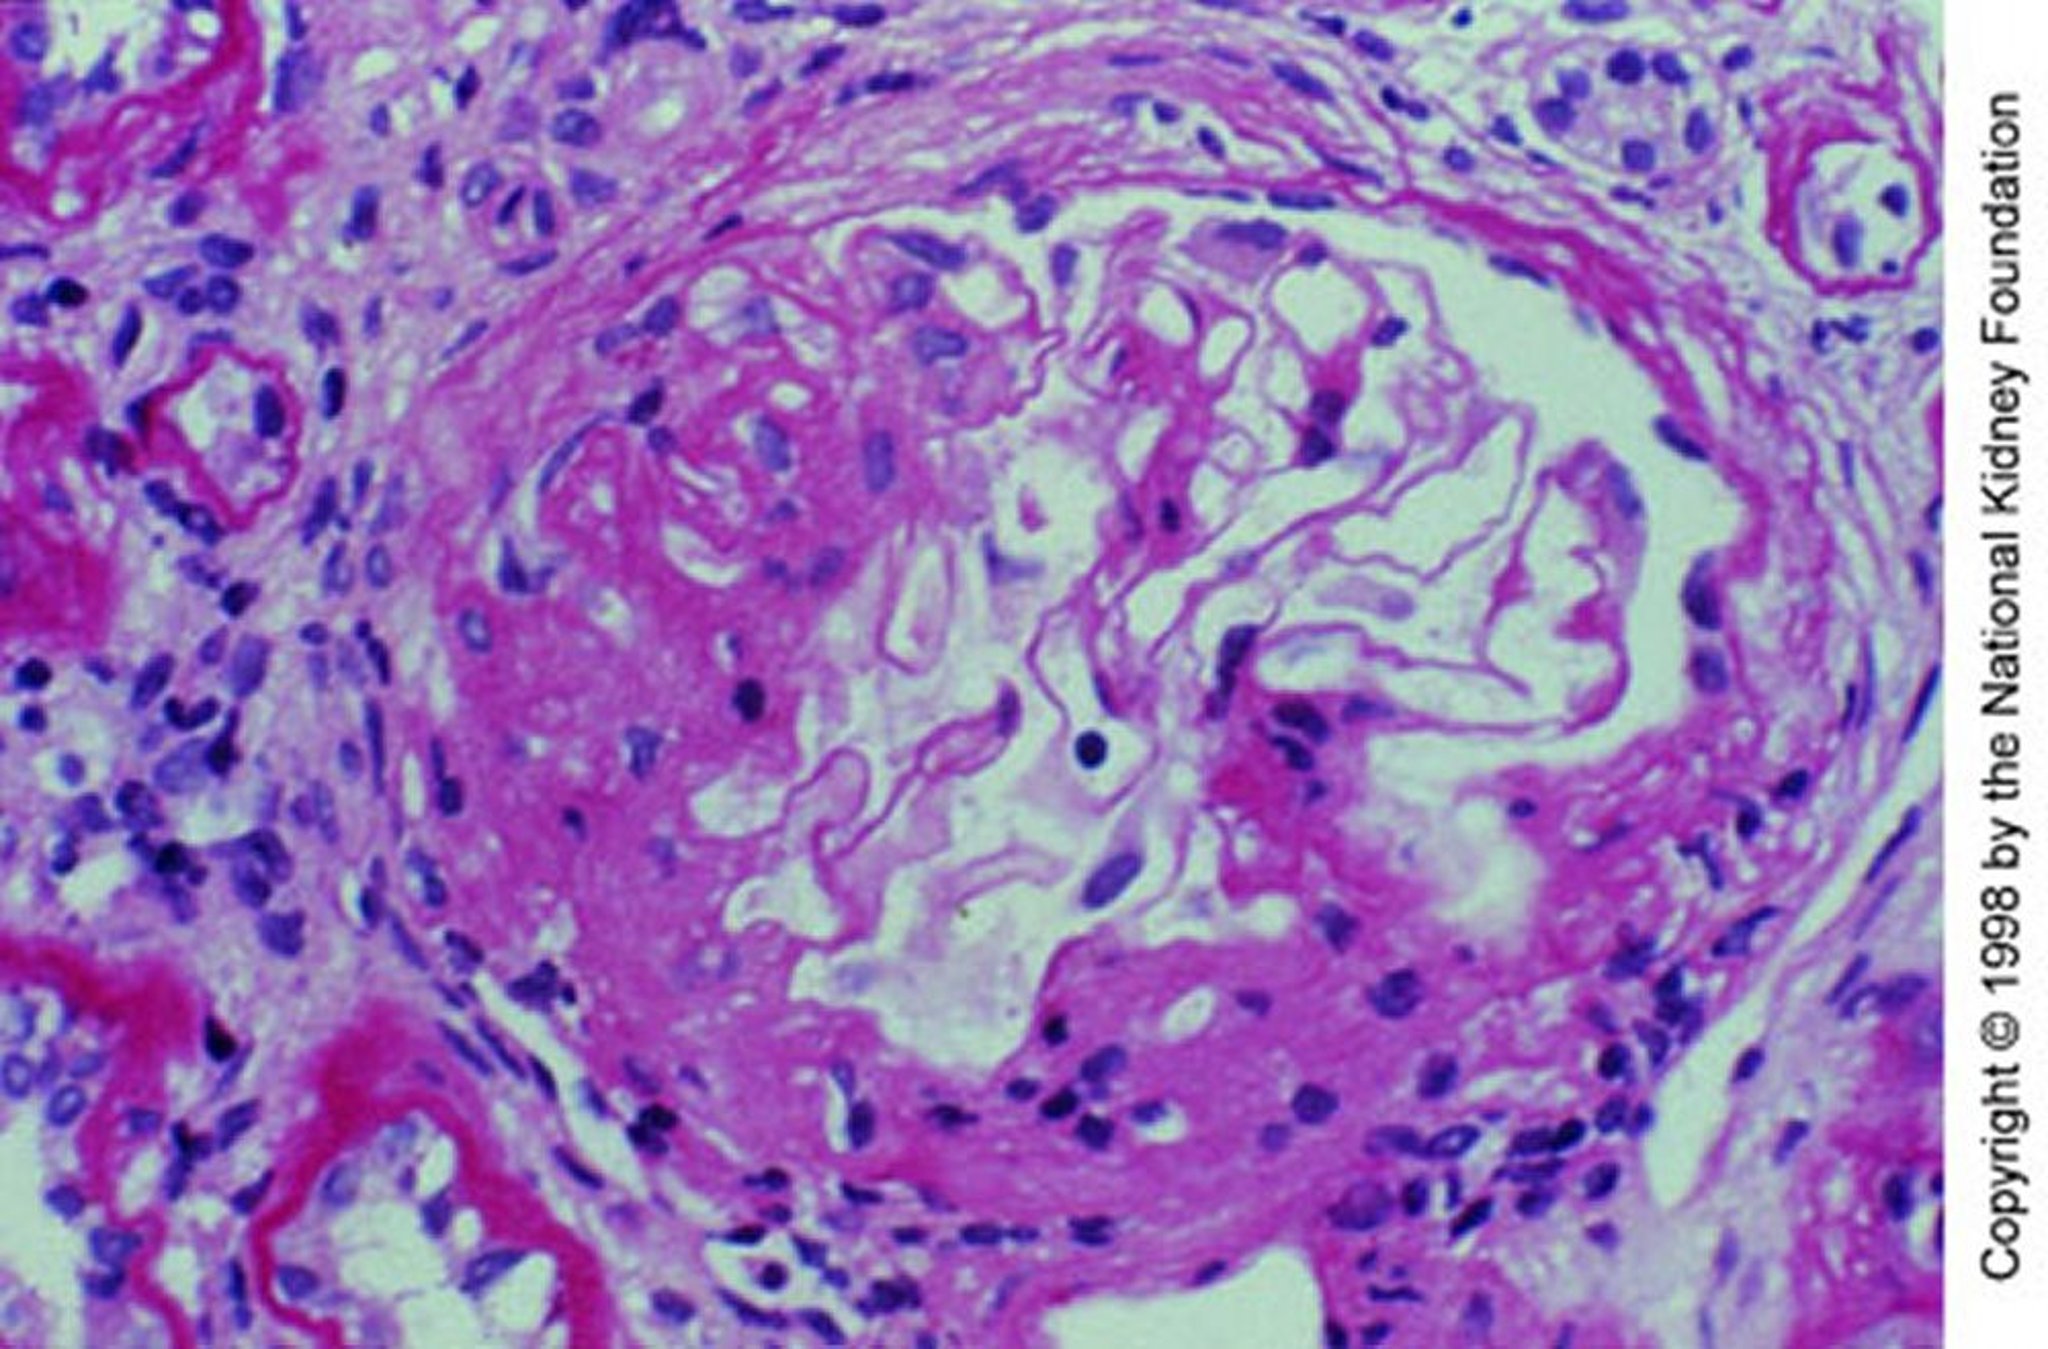

Néphropathie à IgA (expansion mésangiale)

Expansion mésangiale avec sclérose segmentaire (coloration à l'acide périodique Schiff, ×200).

Image fournie par Agnes Fogo, MD, and the American Journal of Kidney Diseases' Atlas of Renal Pathology (voir www.ajkd.org).